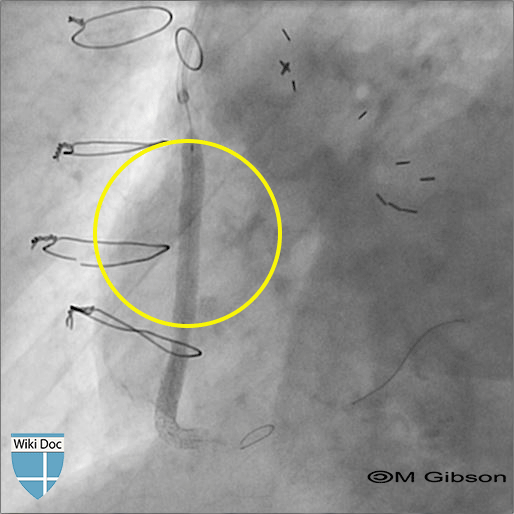

No reflow феномен